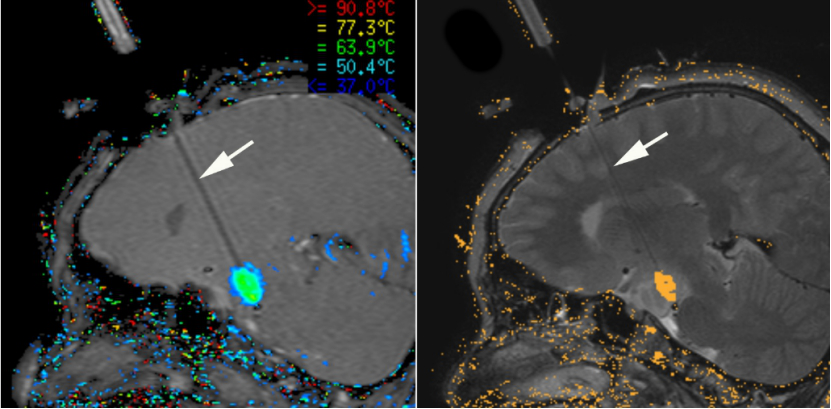

目前已成功欧美兴起的激光间质热疗(LITT),已成为颞叶内侧型癫痫的主要治疗手段之一,其临床应用范围还将进一步拓宽。激光间质热疗(LITT)可以在MR引导下完成操作,实现准确定位、实时监护,且其使用激光探头,探头外面有冷却系统,使用生理盐水降温,可以设置好温度以保护重要组织。激光间质热疗(LITT)可以很好的控制所需温度和毁损的范围,其温度设置在40度以下一般不会毁损,80度以上是立即毁损,60-80度通过时间来控制毁损程度。激光间质热疗(LITT)相对于放射治疗,更准确合适,并发症更少。